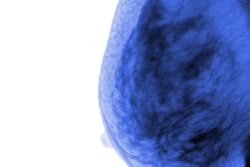

The researchers found that women with a family history of breast cancer had 22% higher odds of having dense breasts.

The study authors also found that women with fatty breasts at baseline mammography who had a family history of breast cancer had 19% higher odds of developing dense breasts (odds ratio, 1.19) compared with women with no family history. Among women with dense breasts, the researchers observed higher odds of women having persistently dense breasts (odds ratio, 1.11) than women without family history.